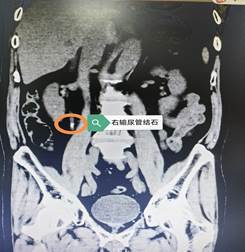

24小时“极速”康复! 一位韩国患者的“中国就医体验”

近日,一位因突发右下腹痛而紧急入院的韩国籍患者,在中西医结合医院泌尿外科体验了一场“速度与温情”并存的就医之旅。从接诊、紧急手术到快速康复出院,全程仅用时不到24小时。科室高效的快速康复流程与无微不至的人文关怀,赢得了这位国际患者的高度赞扬。紧急响应,绿色通道为生命护航当天,这位韩国患者因突发右下腹疼痛,紧急来到院泌尿外科求诊。经检查,确诊为右侧输尿管结石并…